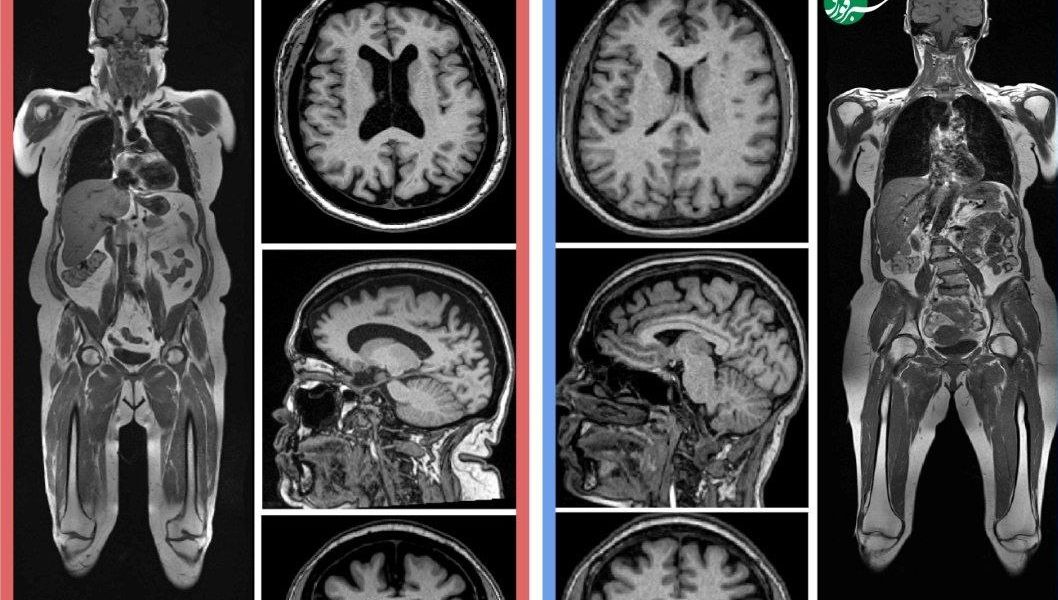

تیم تحقیق تصاویر MRI کل بدن تقریباً ۱۲۰۰ بزرگسال سالم را تجزیه و تحلیل کرد تا «نمایه بدنی» ایده‌آل برای پیری سالم مغز را مشخص کند.

در این مطالعه جدید، تیم او اسکن‌های MRI کل بدن از ۱۱۶۴ مرد و زن سالم با میانگین سنی حدود ۵۵ سال را جمع‌آوری کردند. آنها داده‌های MRI را با فناوری دیگری ترکیب کردند که به بافت‌ها اجازه می‌دهد در نواحی رسوب چربی، روشن و در نواحی غنی از مایع، تیره به نظر برسند.

سپس از الگوریتم‌های هوش مصنوعی برای تعیین میزان عضله و چربی هر فرد (هم چربی زیر پوست و هم چربی جمع شده در اطراف اندام‌ها) و همچنین «سن مغزی» تخمینی آنها استفاده شد.